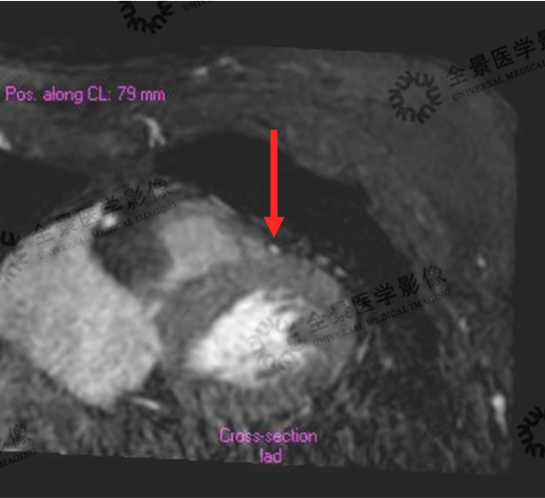

一位中年女性,前胸、后背疼数月,心脏彩超显示无异常,心电图平板运动实验显示为阳性,因自身过敏体质无法做心脏冠脉CTA明确病症,而无创心脏冠状动脉磁共振检查解决了这一问题。

在图像中可以看到前降支中段局限性浅肌桥形成,相应部位管腔未见明显狭窄。目前,该女士正在有针对性地进行治疗。

心脏冠状动脉VR

局限性浅肌桥

此外,天津全景针对心脏提供一站式深入检查,一次扫描可完成心脏结构、心肌活性、心功能、冠状动脉、等部位精密评估,防患未然。